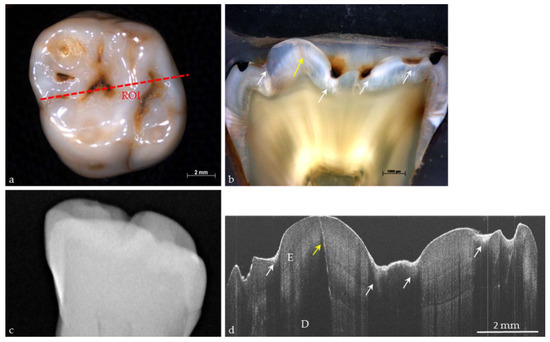

Figure 7. (a) Extracted human molar with occlusal caries (ICDAS II Code 2); (b) In the histological section through ROI, lesions (white arrows) and enamel cracks (yellow arrows) appear; (c) In the conventional digital radiograph no defects or lesions are visible; (d) Bright signals in the OCT image of the ROI demonstrate caries lesions (white arrows) and enamel cracking (yellow arrow). E: enamel; D: dentin.